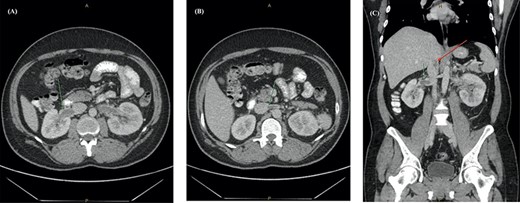

Chest radiograph demonstrated signs of left basal atelectasis, subsequently leading to the diagnosis of community-acquired pneumonia and discharge on oral antibiotics. Given the abdominal pain, other differential diagnoses included pulmonary embolism (PE) and renal colic. PE was excluded at initial presentation using the Pulmonary Embolism Rule-out Criteria (PERC) [4]. Blood work showed a leucocytosis and neutrophilia (Table 1). A computerized tomography urogram (CTU) obtained for suspicion of renal colic showed no renal tract obstruction, subtle right peri-nephric fat stranding and left lower lobe consolidation (Fig. 1).

CT urogram showing (A) right peri-nephric fat stranding (white arrow) with left lower lobe consolidation (red arrow) and (B) transverse section highlighting the left basal consolidation.